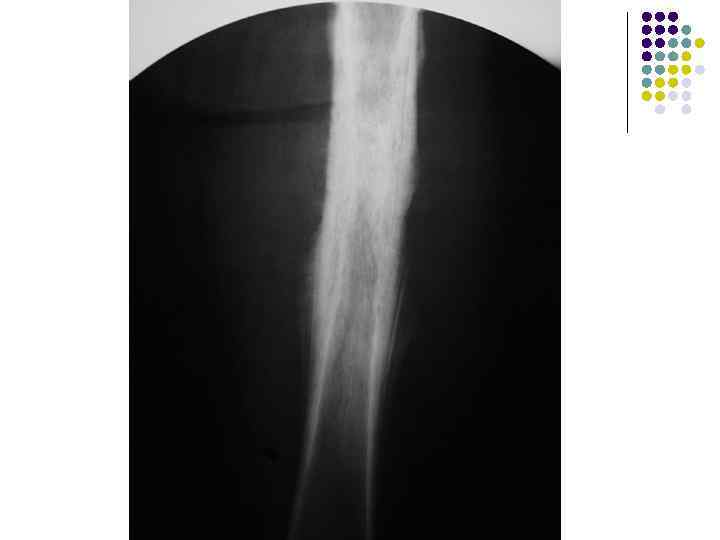

l l На рентгенограмме правой бедренной кости в задней проекции определяется: на уровне средней трети диафиза признаки неравномерного остеосклероза с частичным эностозом, на фоне которых отмечаются явления губчатой деструкции очагового характера без секвестрации. На этом же уровне отмечаются проявления периостальных наложений луковичного, слоистого характера по периферии и игольчатого в центральной части зоны поражения. Увеличение объема мягких тканей с некоторым их уплотнением. Заключение: Учитывая характер патологических изменений (сочетание деструкции и остеосклероза при отсутствии секвестрации), их локализацию (диафизарная часть бедра), особенности периостальных наложений (слоистый характер в периферических участках и игольчатый в центральной зоне), наличие мягкотканного компонента – данные за первичную злокачественную опухоль бедренной кости, вероятнее саркому Юинга.

l l На рентгенограмме правой бедренной кости в задней проекции определяется: на уровне средней трети диафиза признаки неравномерного остеосклероза с частичным эностозом, на фоне которых отмечаются явления губчатой деструкции очагового характера без секвестрации. На этом же уровне отмечаются проявления периостальных наложений луковичного, слоистого характера по периферии и игольчатого в центральной части зоны поражения. Увеличение объема мягких тканей с некоторым их уплотнением. Заключение: Учитывая характер патологических изменений (сочетание деструкции и остеосклероза при отсутствии секвестрации), их локализацию (диафизарная часть бедра), особенности периостальных наложений (слоистый характер в периферических участках и игольчатый в центральной зоне), наличие мягкотканного компонента – данные за первичную злокачественную опухоль бедренной кости, вероятнее саркому Юинга.